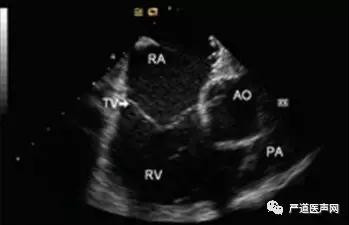

第二步,RA视野调整:继续顺时针旋转导管15°左右,适当推送或回撤导管,可见上方和下方解剖结构,如图3。

图3 RA 位置调整后视野